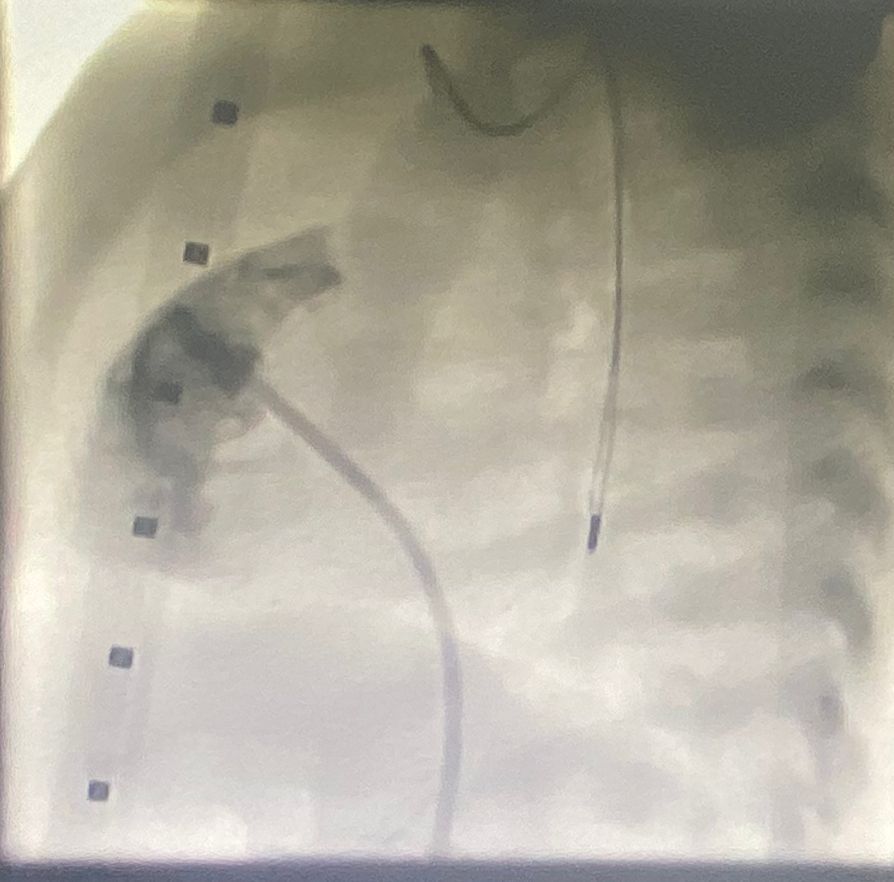

وبين التجمع أن الفريق الطبي بقسم الأطفال في المركز وبعد إتمامالفحوصات والأشعة اللازمة والاطلاع على نتائجها قرر القيام بإجراءالتدخل الطبي العاجل عن طريق تنفيذ عملية قسطرة قلبية عالية الدقة، تمخلالها توسيع الصمام الرئوي ليتدفق الدم من خلاله إلى الرئتين، وقدوتكللت القسطرة بالنجاح ولله الحمد